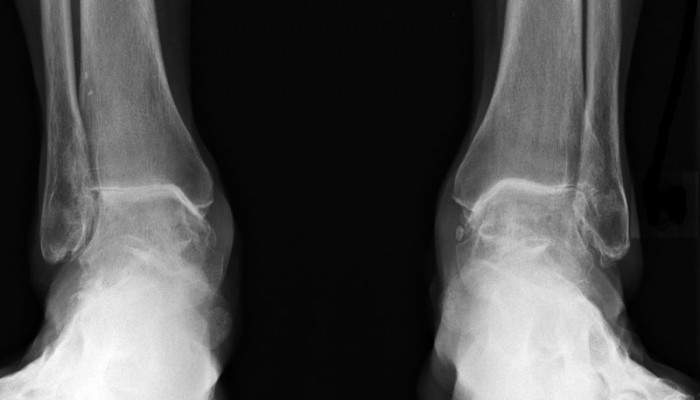

Вторая степень ДОА диагностируется как визуально, так и на рентгене. При наружном осмотре заметно увеличение сустава, его движение ограничено, хорошо слышен хруст. На рентгене диагностируется уменьшение суставной щели на 50%. Опытный врач обязательно назначит рентген в боковой проекции. На нём будет видна таранная кость. При деформирующем остеоартрозе она уплощена, а её суставная поверхность увеличена.

- Рентгена. На нём будет видно, в каком состоянии хрящ, как наклонена ось больного сустава, поражены ли близлежащие суставы. На основании картины специалист поймёт, что стало причиной начала дегенеративных процессов.